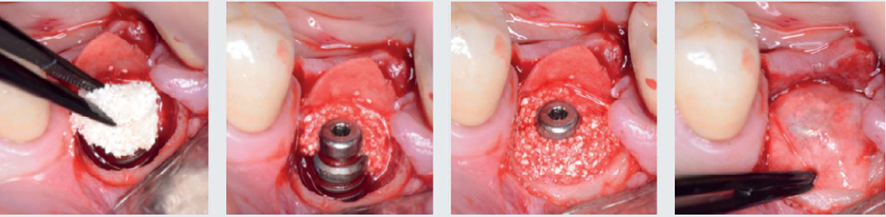

A abordagem cirúrgica proposta foi realizada com retalho total, preservando as papilas adjacentes através de incisões sobre a crista e proximais relaxantes, seguida de desbridamento com curetas metálicas periodontais convencionais e pontas ultrassônicas diamantadas piezocirúrgicas (Figura 2). Em seguida, após a instrumentação mecânica descrita, foi utilizado jato de bicarbonato de sódio + ácido fosfórico 37% (dois minutos) + EDTA 24% (dois minutos) + irrigação com solução salina para descontaminação da superfície do implante (Figura 3). Finalizada a descontaminação, foi colocado um parafuso de cobertura com 1,5 mm para permitir o fechamento primário do retalho e uma posterior reentrada sem exposição tecidual excessiva. Devido às características morfológicas intraósseas do defeito serem favoráveis à regeneração, foi realizado enxerto ósseo com substituto ósseo xenógeno Extra Graft XG-13 (75% de hidroxiapatita natural bovina + 25% de colágeno) associado ao Endogain (matriz derivada do esmalte). As excelentes propriedades hidrofílicas do Extra Graft, junto às proteínas amelogeninas do Endogain, proporcionaram um enxerto com fácil manuseio e propriedades osteocondutivas. Além disso, podem melhorar o potencial biológico para neoformação óssea em um ambiente fisicamente estável e protegido pela membrana de colágeno. Após o completo preenchimento até o nível vertical dos limites circunferenciais, o enxerto foi coberto com uma membrana de colágeno natural bovino (Figura 4).